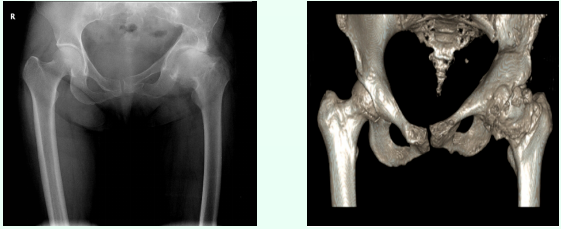

日前,我院应用3D打印技术辅助一名左侧创伤性股骨头坏死患者成功实施“左侧人工全髋关节置换”手术,解除患者二十余年的疼痛,助其恢复正常行走。

阅读次数:5789